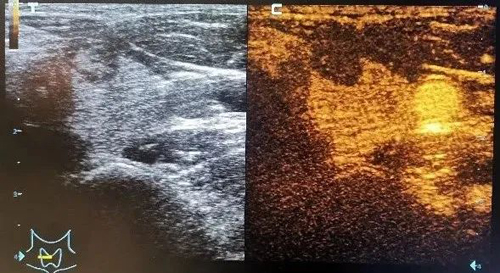

随着技术的进步,目前对甲状腺结节还可以进行弹性成像的评估以及造影的检查,对于甲状腺结节的诊断及治疗都有重要的意义。

术后造影